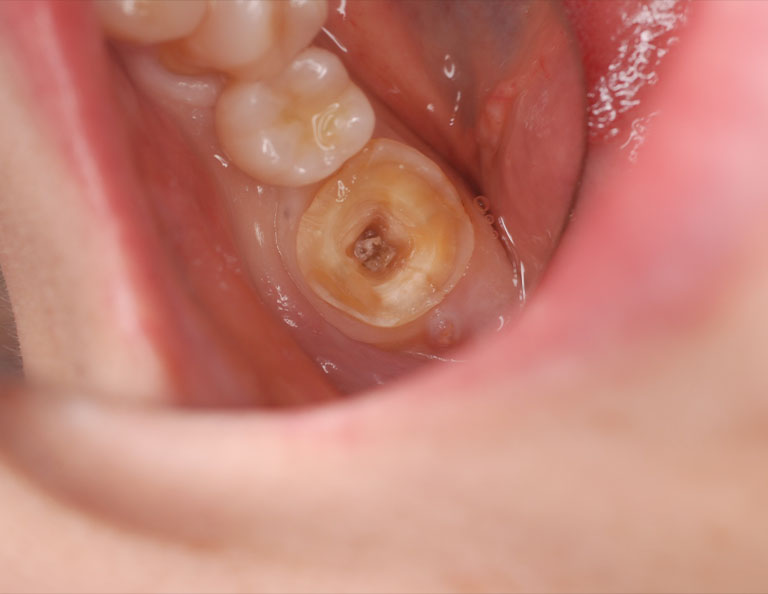

右下第二大臼歯が腫れたということで来院されました。レントゲンおよびCT撮影をしたところ、根っこの先および周囲が黒く抜けており、神経が死んでしまい膿が溜まっている状態でした。被せ物を外したところ歯にヒビが確認できましたが、何とか保存できると判断し、樹脂で補強した後、ラバーダム防湿下で根管治療を行いました。 |

初診時の状態です。歯肉に腫脹が認められます。

被せ物を外すと歯の神経である歯髄は死んでしまっており、歯に亀裂も認められます。

亀裂を樹脂で補強し、ラバーダム防湿下で根管治療を開始しました。